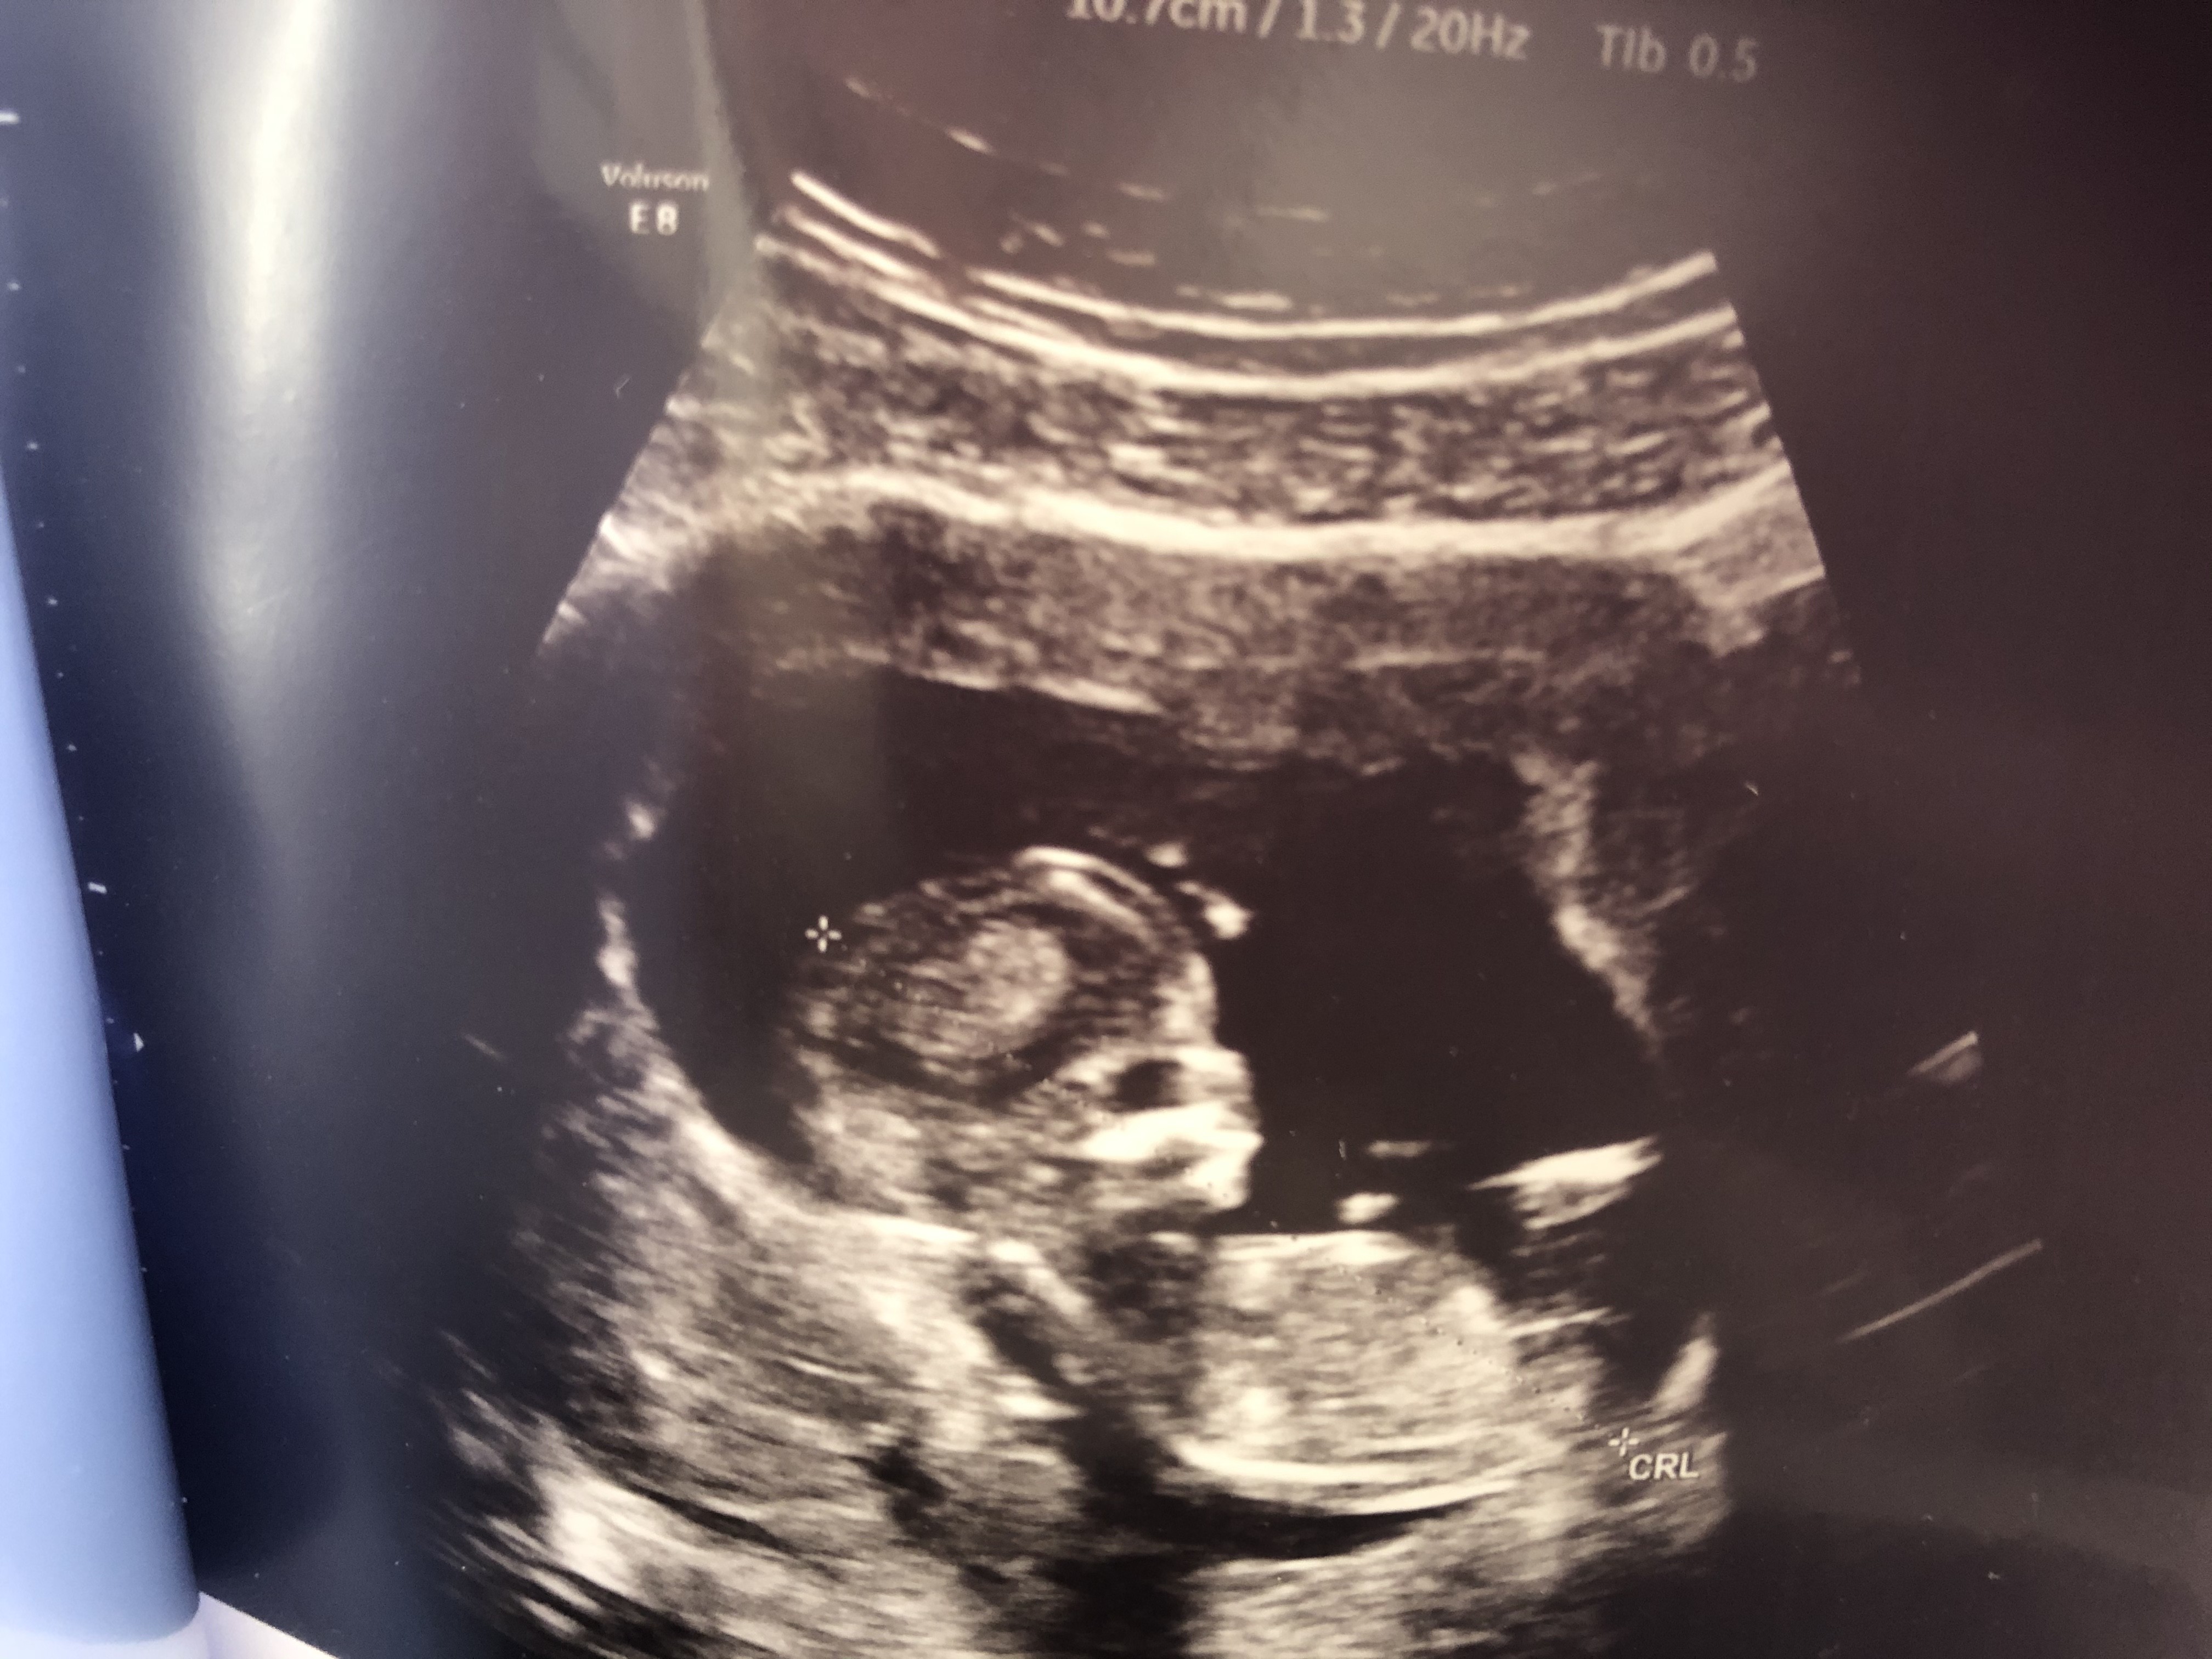

Usg chłopak czy dziewczynka

Witam w 19 tygodniu ciąży dowiedziałam się ze będę miała dziewczynkę w 20 tyg okazało się jednak , że to chłopak. Sama już nie wiem bo na jednym usg widać na pewno dziewuche a na drugim chłopca. Może to pempowina ?? Może ktoś mi pomoże rozwiązać ta zagadkę